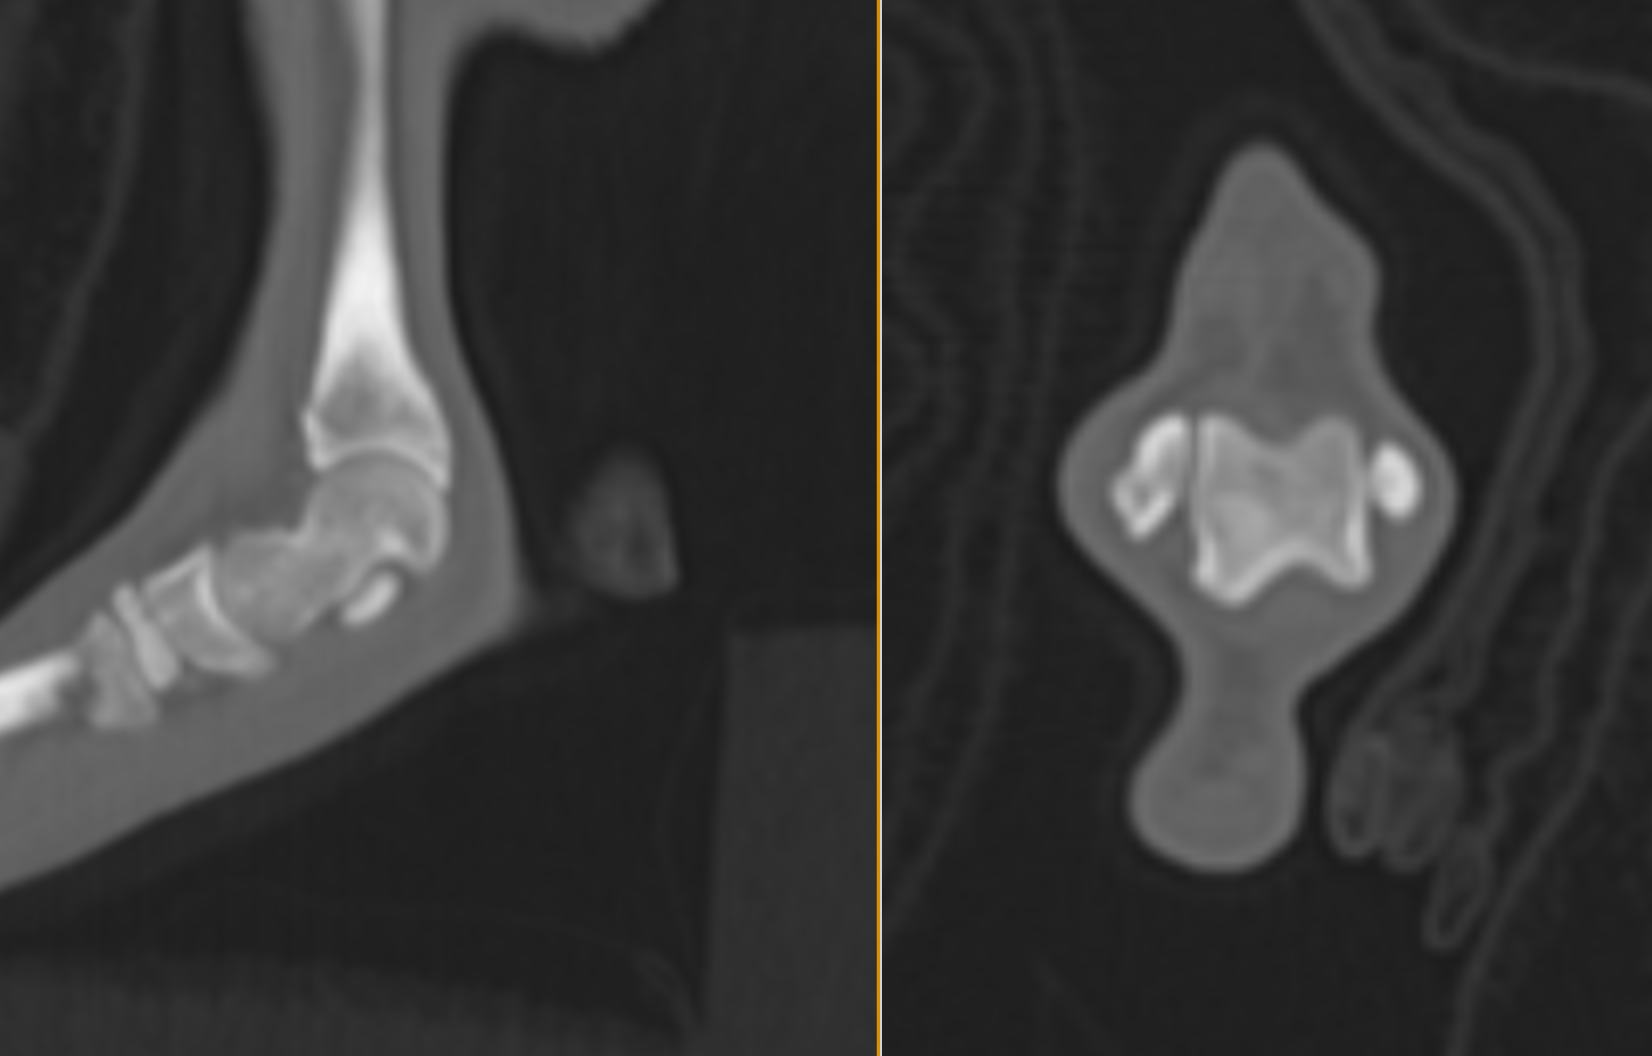

CT画像のMPRです(3方向で切って確認する画像)。矢印の部分が遊離骨片です。